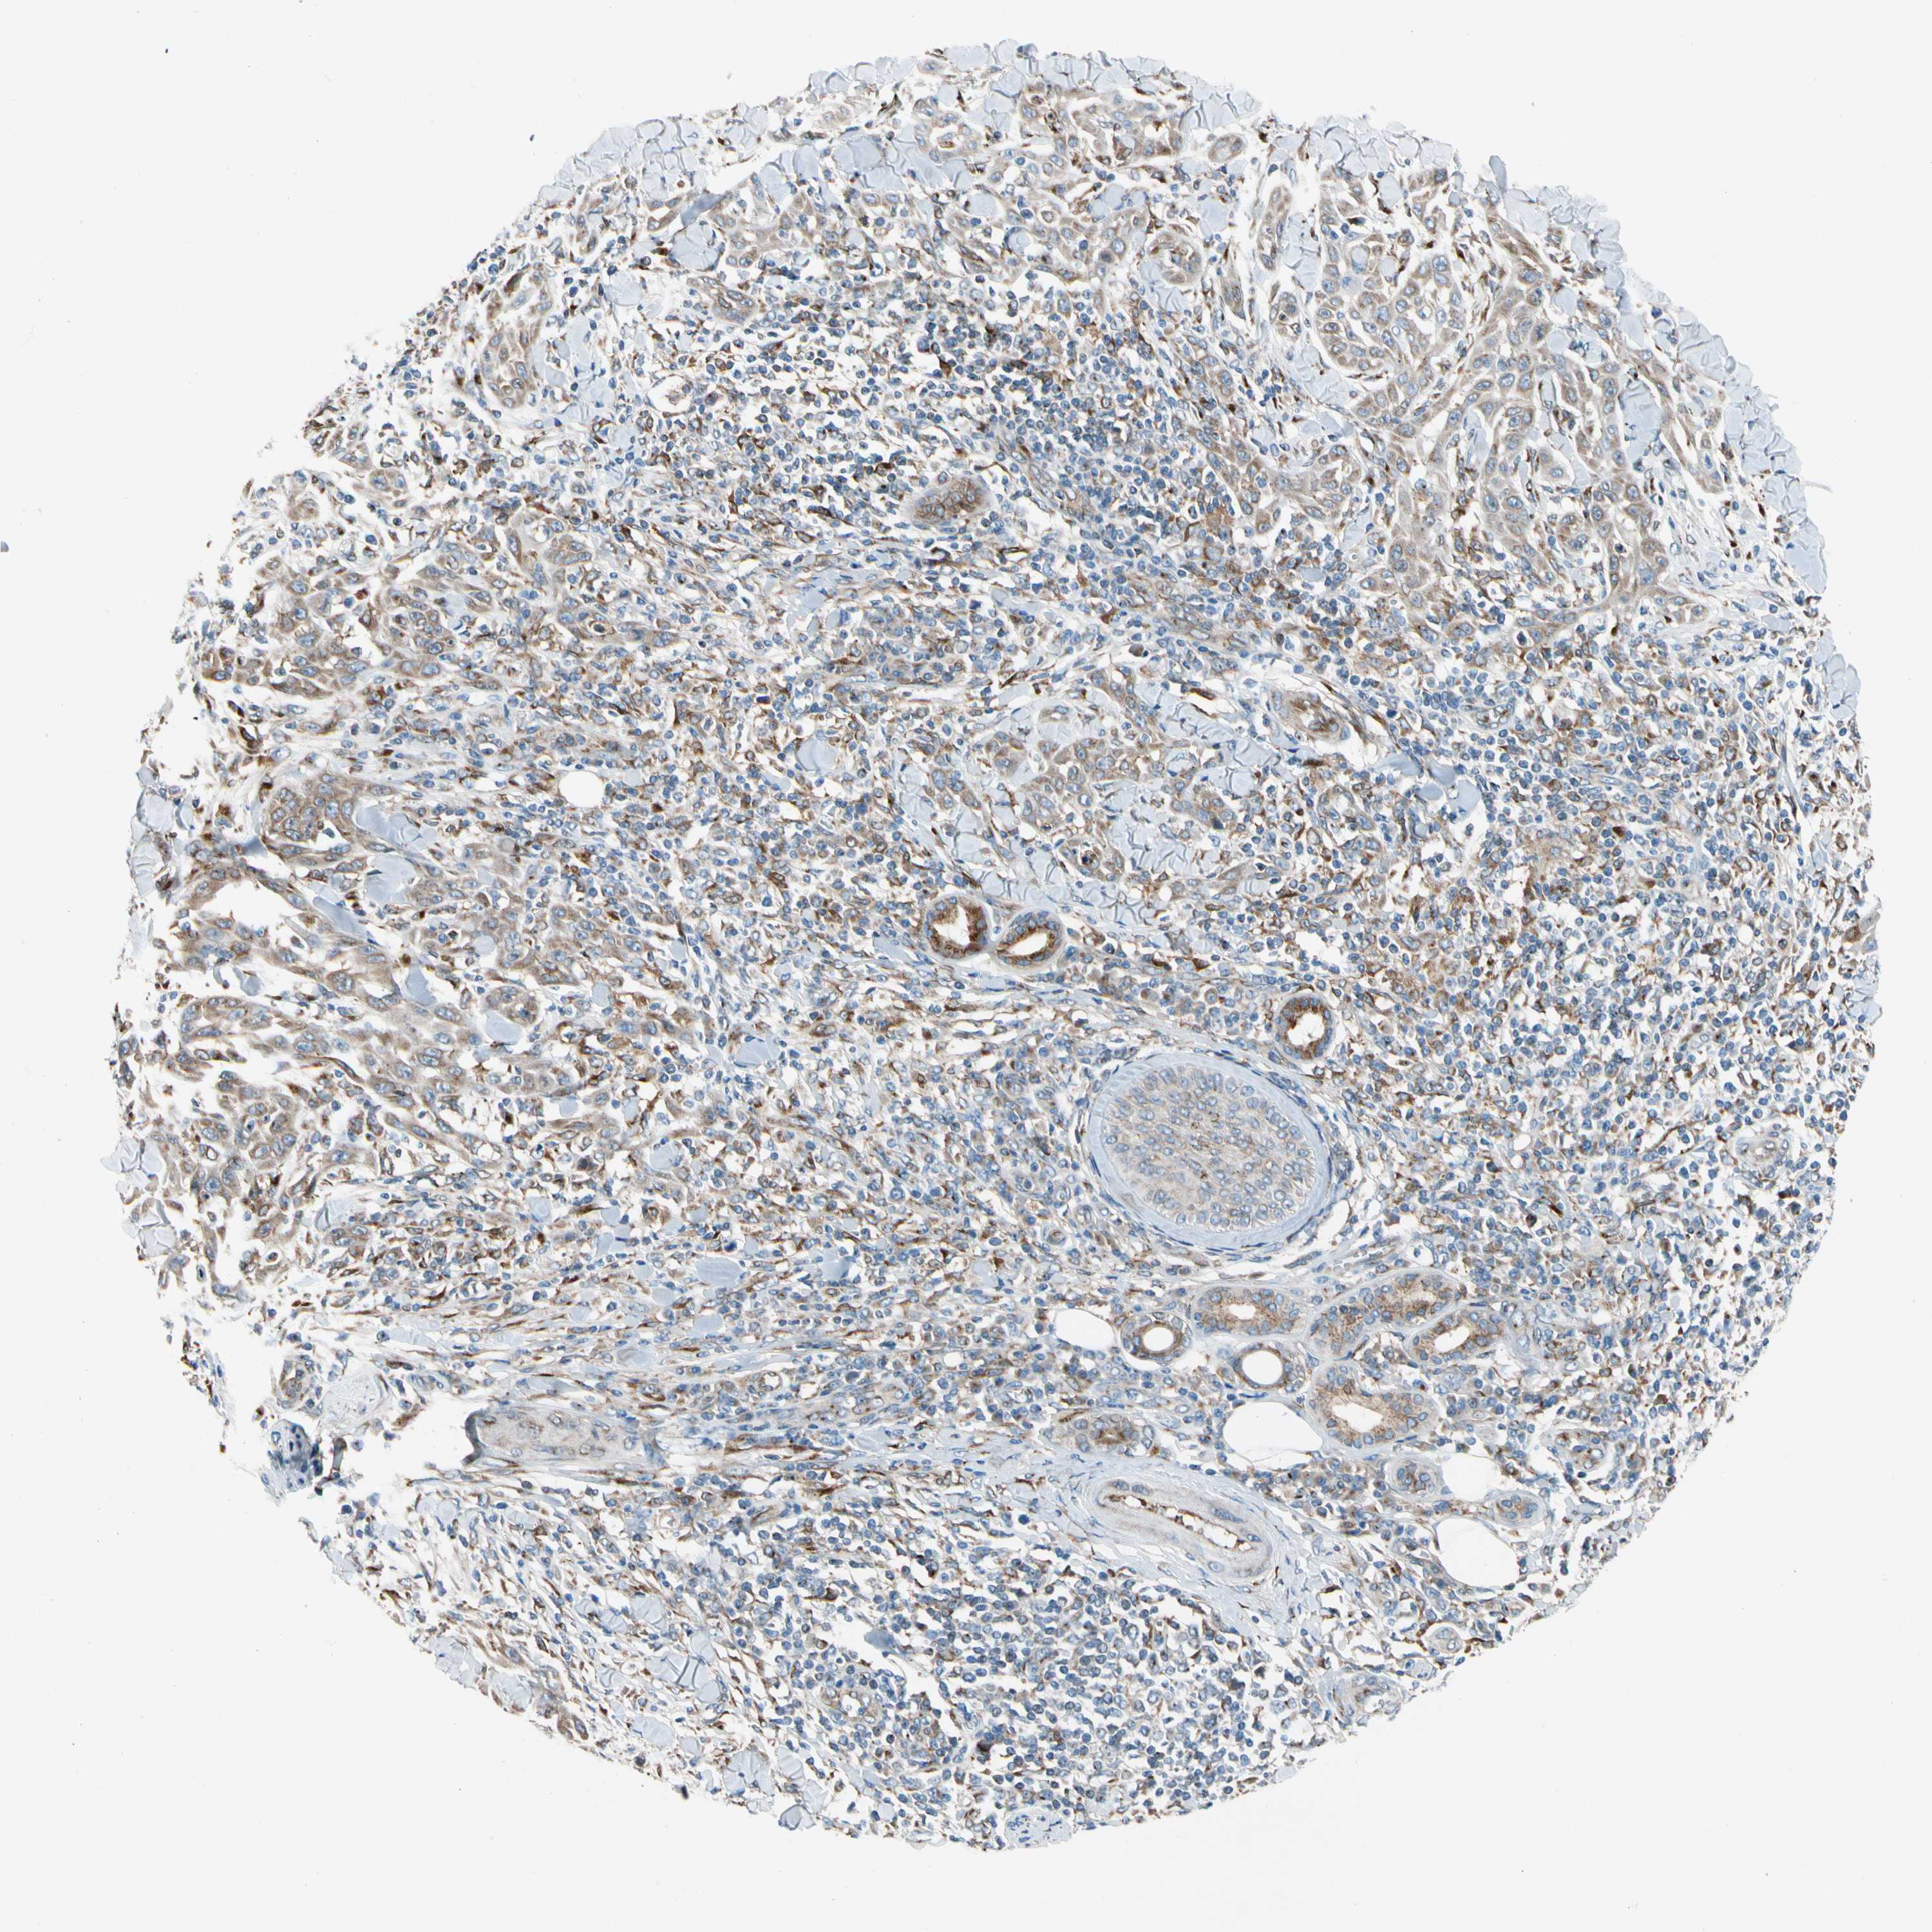

SKIN CANCER - Protein expressioni

A mouse-over function shows sample information and annotation data. Click on an image to view it in a full screen mode. Samples can be filtered based on level of antibody staining by selecting one or several of the following categories: high, medium, low and not detected. The assay and annotation is described here.

Antibody stainingi

Antibody staining in the annotated cell types in the current human tissue is reported as not detected, low, medium, or high, based on conventional immunohistochemistry profiling in selected tissues. This score is based on the combination of the staining intensity and fraction of stained cells.

Each image is clickable and will lead to virtual microscopy that enables deeper exploration of all samples and also displays staining intensity scores, fraction scores and subcellular localization as well as patient and tissue information for each sample.

Antibody HPA008176

Staining

High

Medium

Low

Not detected

Intensity

Strong

Moderate

Weak

Negative

Quantity

>75%

75%-25%

<25%

None

Location

Nuclear

Cytoplasmic/membranous

Cytoplasmic/membranous,nuclear

Squamous cell carcinoma, NOS

Basal cell carcinoma